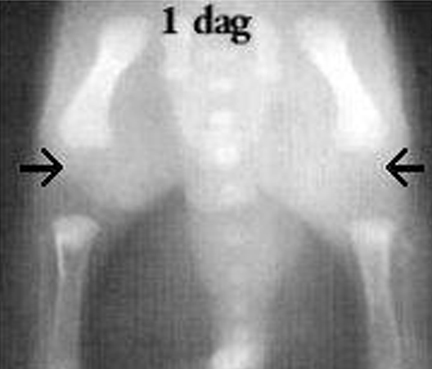

RTG znázorňujúce vývoj kĺbov v štenacom veku.

Vek psa - 1deň

w heupen pup 1 dag oud